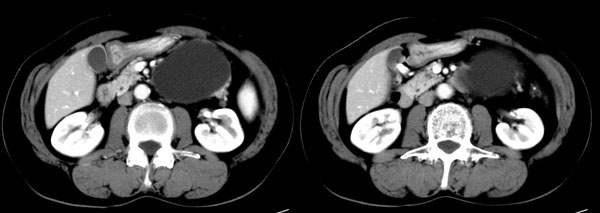

参照ct片,经皮穿刺,抽出透明液体60ml,随后置入引流管引流,囊液细胞学检查阴性,胰酶检查阴性。采用无水乙醇灌注治疗。4天后囊腔闭锁,无液体渗出,予以拔管。

置管后造影,显示囊腔直径约5cm,囊壁光整,正位、双斜位造影均未见造影剂外溢,与胰腺无交通